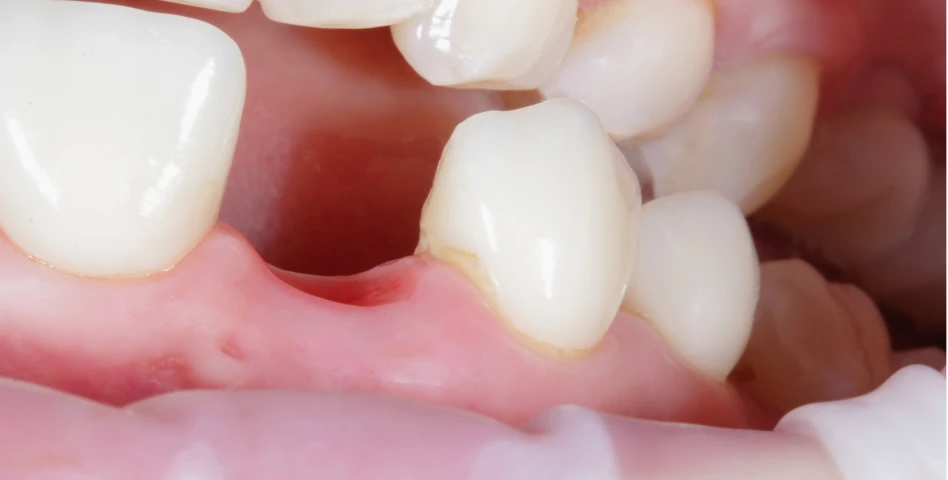

Les implants préservent l’os et ne nécessitent pas de tailler les dents voisines. Ils offrent une solution stable et durable.